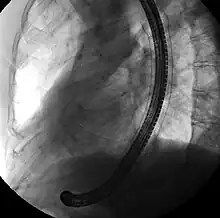

![]() Endoscopic view of a self-expandable metallic stent used to palliate an esophageal cancer | |

A self-expandable metallic stent (or SEMS) is a metallic tube, or stent that holds open a structure in the gastrointestinal tract to allow the passage of food, chyme, stool, or other secretions related to digestion. Surgeons insert SEMS by endoscopy, inserting a fibre optic camera—either through the mouth or colon—to reach an area of narrowing. As such, it is termed an endoprosthesis. SEMS can also be inserted using fluoroscopy where the surgeon uses an X-ray image to guide insertion, or as an adjunct to endoscopy.

The vast majority of SEMS are used to alleviate symptoms caused by cancers of the gastrointestinal tract that obstruct the interior of the tube-like (or luminal) structures of the bowel — namely the esophagus, duodenum, common bile duct and colon. SEMS are designed to be permanent and, as a result, are often used when the cancer is at an advanced stage and cannot be removed by surgery.